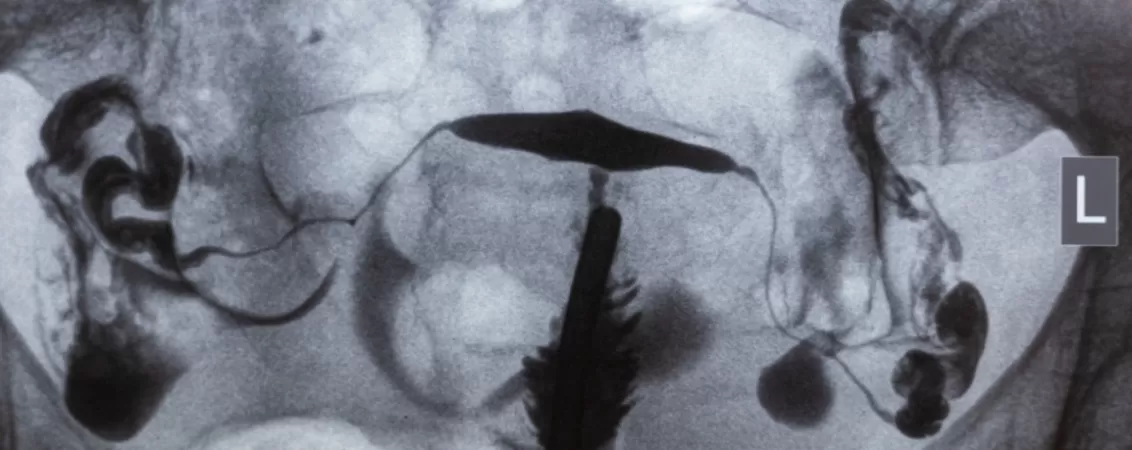

- Radiografie cu bariu – pentru explorarea tractului digestiv (esofag, stomac, intestin subțire și gros). Substanța folosită este sulfatul de bariu, administrată oral sau rectal;

- Angiografie – pentru vizualizarea vaselor de sânge și detectarea stenozelor, anevrismelor sau blocajelor. Substanța utilizată pe bază de iod este administrată direct în vase;